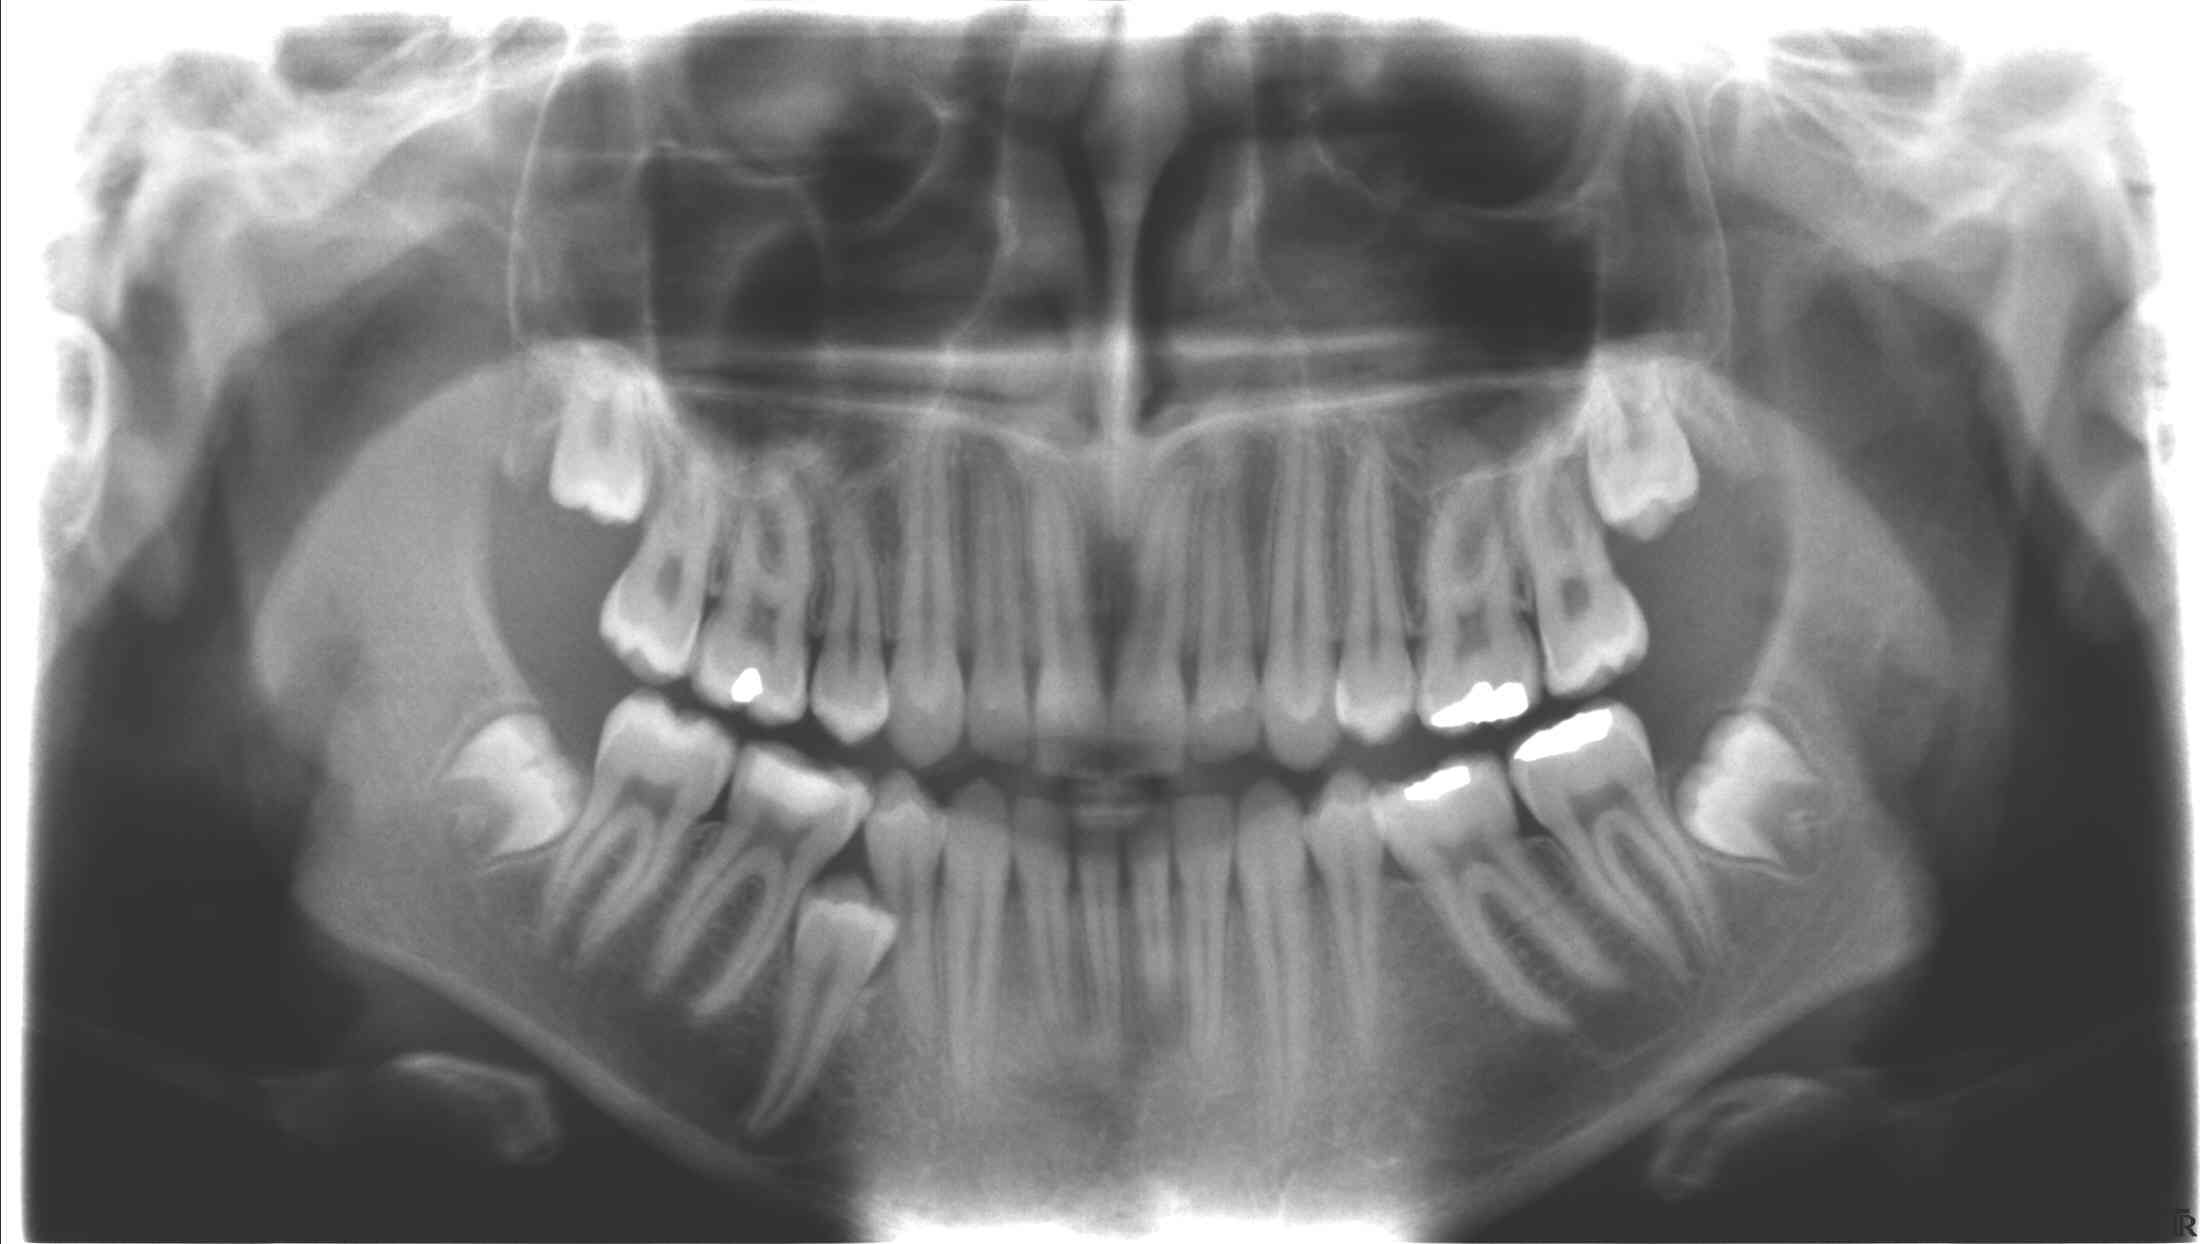

V jakém stavu jsou jednotlivé zuby

Digitální RTG snímky, kontrola dásní a analýzu skusu

Proběhne kontrola zubů, dásní a celkového stavu dutiny ústní.